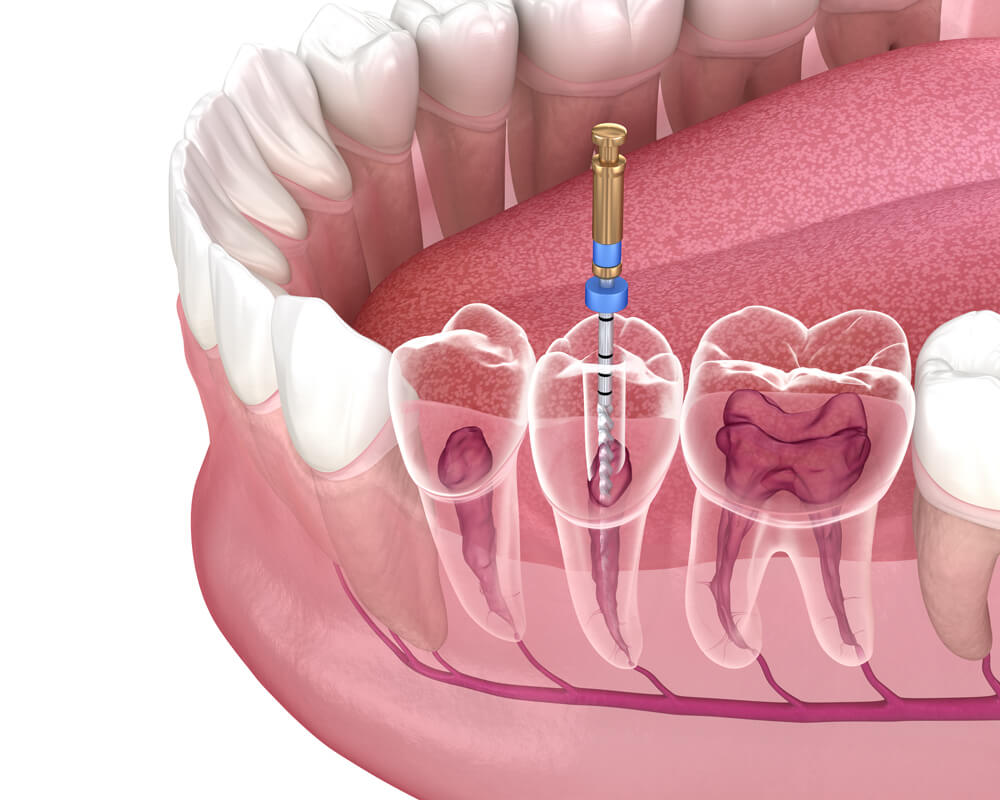

The decaying of teeth (cavities), if left untreated, develop further and gradually destroy a significant portion of the tooth before reaching the ‘pulp’ of the tooth. This pulp is a thin and soft tissue present in the tooth canals, predominantly consisting of nerves and blood vessels. If the infection reaches the pulp, it results in what is commonly known as ‘dental pain’. At this stage, the tooth can only be saved by performing a root canal treatment.

1. 3D Imaging & Diagnosis

Modern tech allows us to understand the anatomy of your tooth to treat it correctly.

2. Remove the Infection

We’ll remove decay, clean and disinfect your canal system, and seal the canal.

3. Restoring the Tooth

We’ll design a custom crown to cover and protect the tooth, restoring beauty and function.